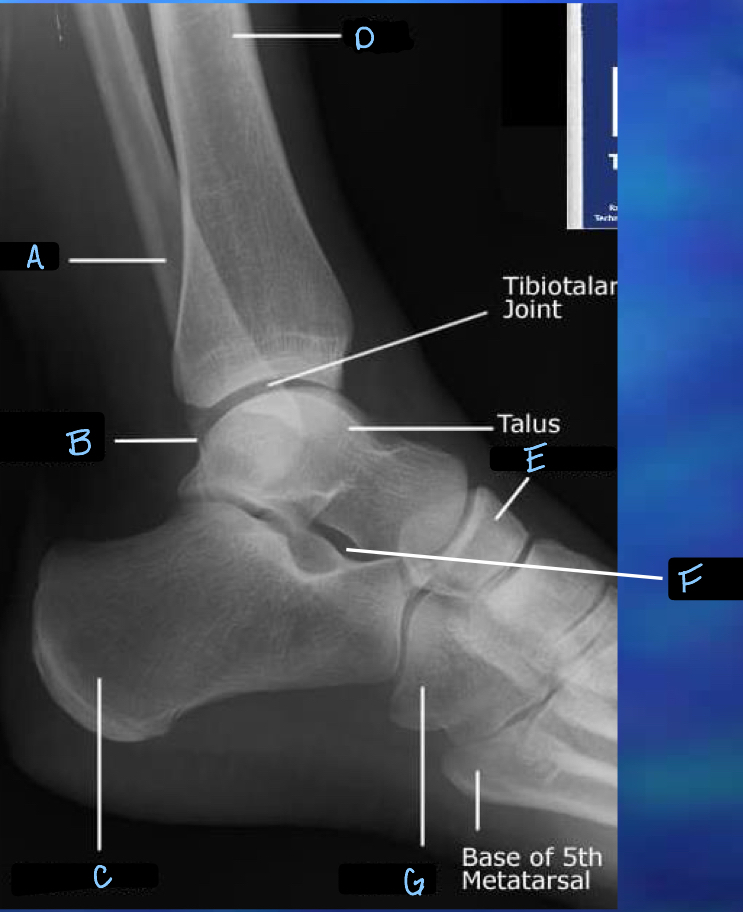

What is A?

tibia

What is B?

tibotalar joint

33

tarsals

What is D?

metatarsals

35

phalanges

What is F?

sesamoid bones

37

navicular

What is H?

sinus tarsi

What is I?

calcaneum

What is J?